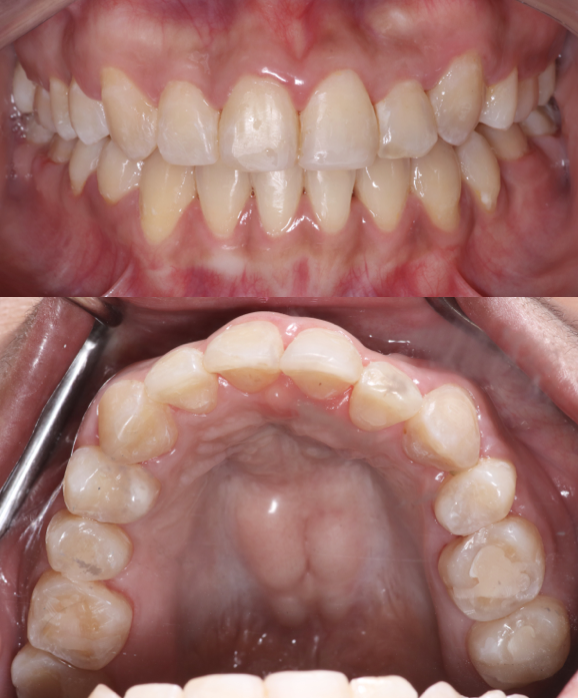

Before

After

BRACES - SEVERE CROWDING

This patient had severe dental crowding with overlapping and rotated teeth that affected both smile aesthetics and bite function. Through comprehensive orthodontic treatment with braces performed by the Moral Dental Clinic team, the teeth were carefully aligned, arch form restored, and bite improved. The final result shows a beautiful, balanced smile with better oral function, easier cleaning, and long-term stability